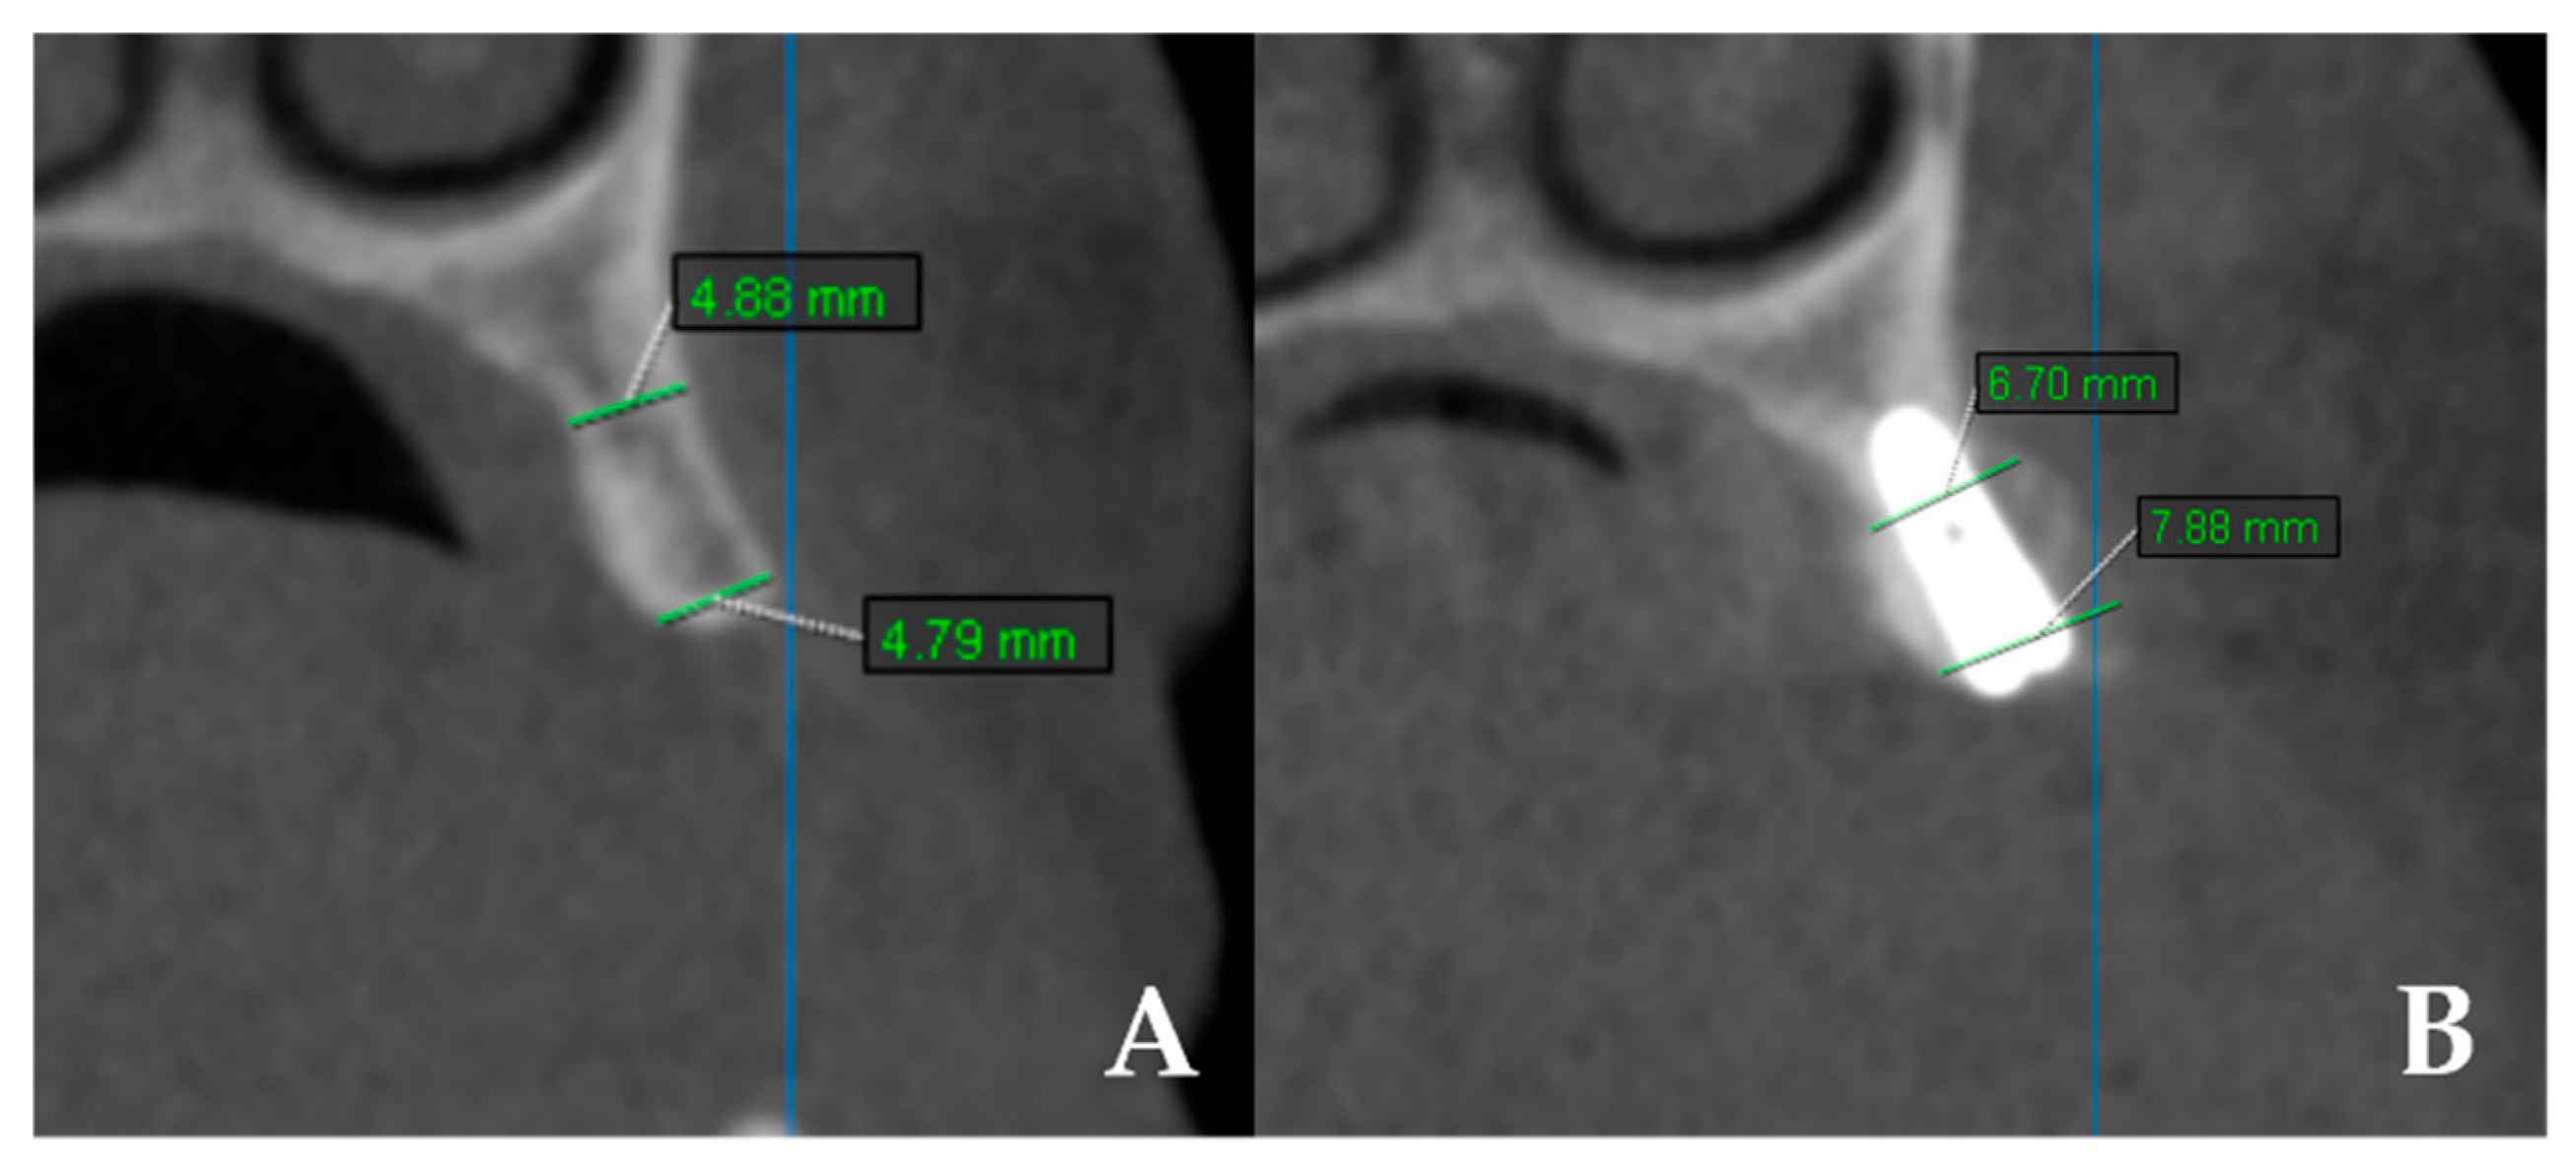

- Bone width: CBCT scans (KaVo OP 3D Vision, Imaging Sciences International LLC, Hatfield, PA, USA) were obtained preoperatively and at 4 months. Measurements were performed at coronal and apical levels using OnDemand 3D App v1.0 (Cybermed Inc., Daejeon, Republic of Korea). The difference between baseline and 4 months was recorded as “bone gain” (Figure 3). All measurements were performed twice by a single examiner, with intra-observer reliability exceeding 90%.

Figure 3. CBCT images showing linear measurements of ridge width before and after surgery. (A) Preoperative measurements of horizontal ridge width. (B) Postoperative measurements of horizontal ridge width.

3.3. Bone Width and Bone Gain

In this study, horizontal ridge width was measured at both the coronal and apical levels. Tomographic measurements were recorded in millimeters at three time points: preoperatively (preop), postoperatively (postop), and as bone gain (difference between the two). To compare the osseodensification and control groups, bone gain values (mm) were calculated by subtracting the preoperative ridge width from the postoperative measurements. Statistical analyses were then performed to assess significant differences in bone gain between the groups and between the coronal and apical regions.

No statistically significant differences were observed between the groups regarding preoperative ridge width at coronal and apical levels (p > 0.05). This finding indicates that both groups initially presented with comparable ridge widths, suggesting that the comparisons were conducted under equivalent baseline conditions. Regarding bone gain, the mean increase in the coronal region was 2.81 mm in the OD group and 2.99 mm in the control group. In the apical region, the mean bone gain was 0.73 mm in the OD group and 1.37 mm in the control group. Although the control group exhibited slightly greater bone gain than the OD group at both the coronal and apical levels, the differences were not statistically significant (p > 0.05) [Table 3].

However, intragroup comparisons revealed that both the OD and control groups demonstrated significantly greater bone gain at the coronal level compared with the apical level (p = 0.001; p < 0.01) [Table 3] (Figure 4).